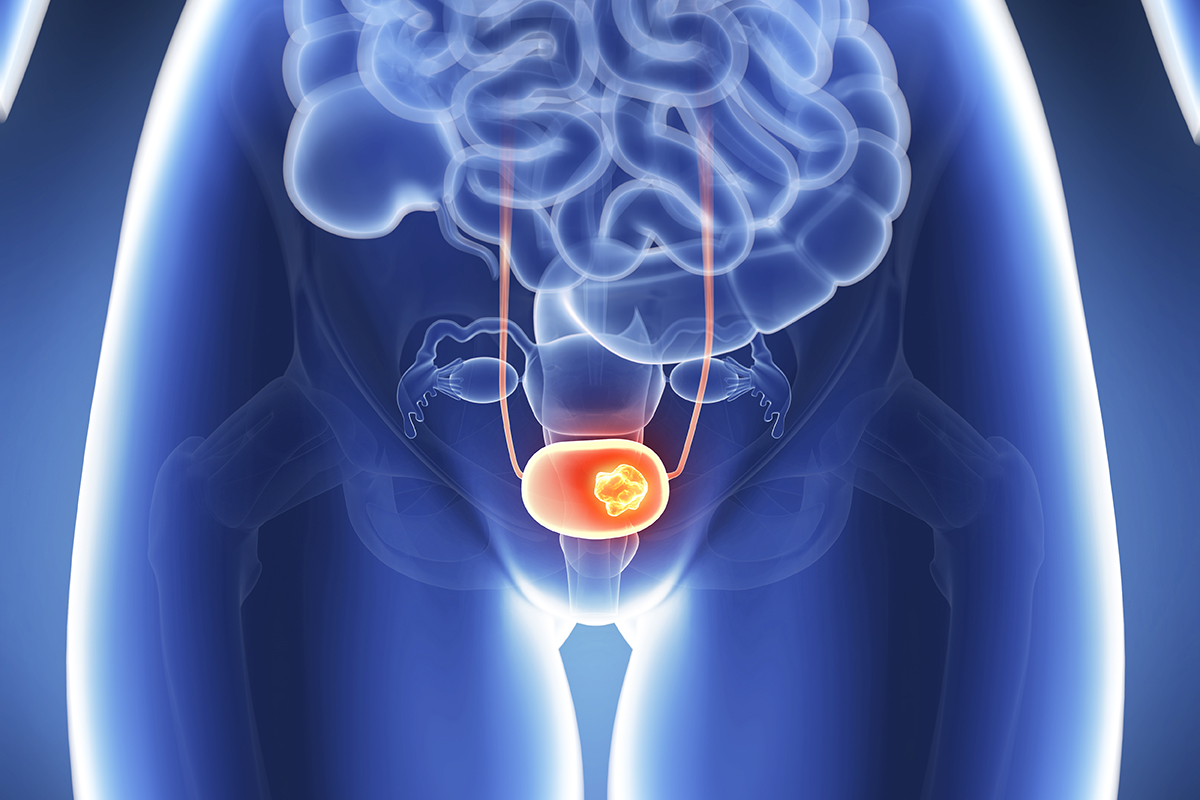

Ο καρκίνος στην ουροδόχο κύστη θα πρέπει να γνωρίζετε πως είναι εξαιρετικά «ύπουλος», καθώς τα συμπτώματα με τα οποία εκδηλώνεται μοιάζουν με αυτά όπως της ουρολοίμωξης.

Συμπερασματικά, τα συμπτώματα που περιγράψαμε παραπάνω θα μπορούσαν να είναι απολύτως ακίνδυνα ή ενδεικτικά μιας λιγότερο σοβαρής κατάστασης.

Ακόμα, θα πρέπει να κάνετε τις κατάλληλες ιατρικές εξετάσεις για να διαπιστώσετε εάν μπορεί να σχετίζονται με τον καρκίνο της ουροδόχου κύστης. Όπως και άλλες μορφές αυτής της ασθένειας, η ταχεία ανίχνευση είναι το κλειδί για μια επιτυχή θεραπεία.